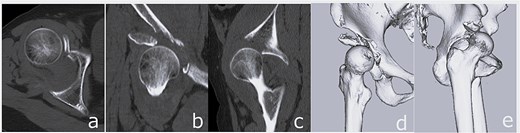

Closed reduction was performed under sedation. Post-reduction imaging showed incarceration of the femoral head fragment within the acetabulum and partial deficiency of the anterior roof arc (Fig. 3). Acute THA was scheduled 7 days after injury. Preoperative planning was based on careful evaluation of three-dimensional CT images. Although a dedicated three-dimensional templating system was not available at our institution, fracture lines, bone defects, and the expected acetabular coverage were assessed visually using multiplanar and three-dimensional reconstructed CT images. Based on this assessment, we anticipated that sufficient rim engagement and primary stability of a cementless cup could be achieved without additional internal fixation.

Post-reduction imaging: Anteroposterior radiograph (a) and CT images (b–d) demonstrating reduction of the hip joint with an intra-articular femoral head fracture fragment and anterior acetabular wall involvement.